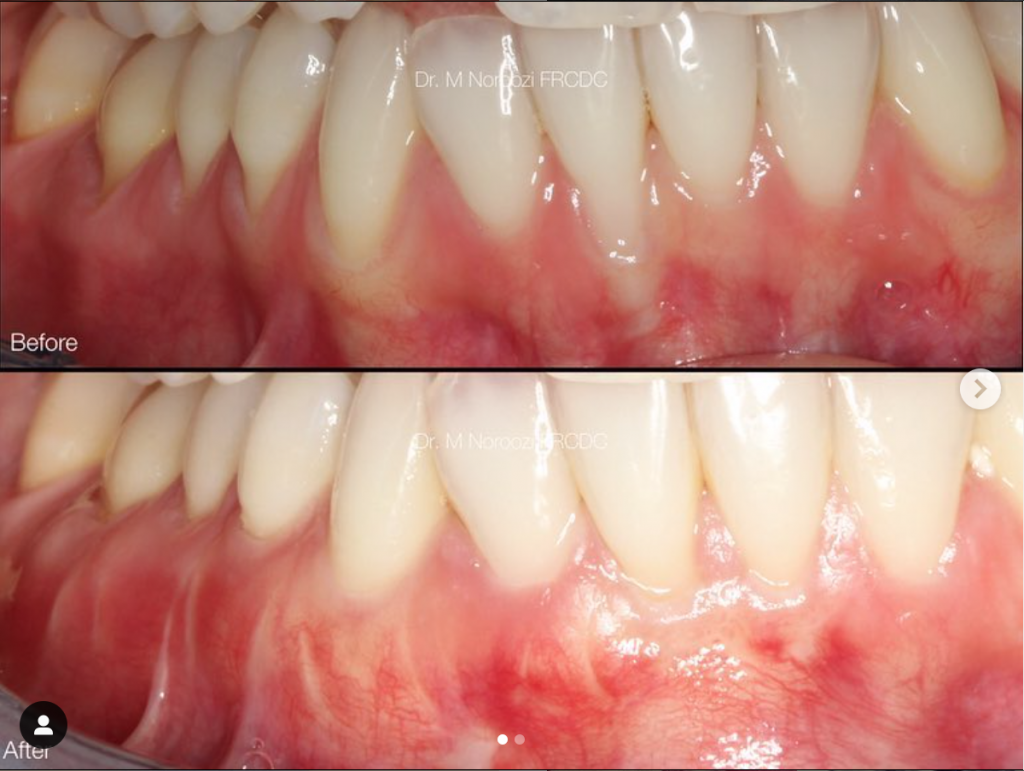

Dr. Mehdi Noroozi, certified Pinhole clinician, performs revolutionary Pinhole® Surgical Technique with application of allograft dermal matrix as an alternative to traditional gum grafting at IMPrESS Perio Implant Center located in Burnaby BC for treatment of gum recessions predictably, safely and minimally invasive. Learn more about our specialist here.

During the Chao Pinhole® Surgical Technique, a needle is used to make a small hole in the patient’s existing gum tissue. Through this pinhole, special instruments are used to gently loosen the gum tissue. These tools help expand and slide the gumline to cover the exposed root structure. There are no grafts, no or minimal sutures, and no incisions needed with the Chao Pinhole® Surgical Technique. It simply involves the adjustment of the existing tissue and thickening of the gingival biotype (Gum) through the placement of collagen or acellular dermal matrix (alloderm).

General Disclaimer: The results in the photographs are examples only and do not imply any certainty of the result of a procedure, and all outcomes are subject to the circumstances of the individual patient.